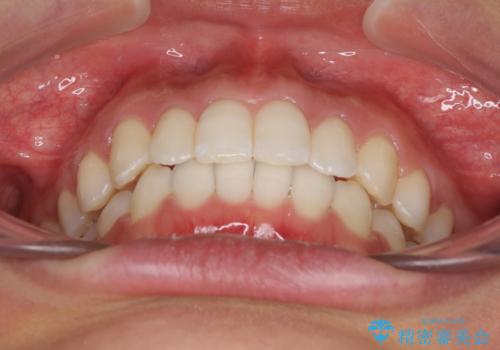

- 深い咬み合わせ(ディープバイト)と前歯のデコボコを気にして来院された患者様です。

インビザラインによる上下歯列の側方拡大と後方移動、IPR(歯と歯の間を削る)にるスペースの獲得により、デコボコとディープバイトを改善することとしました。

1日22時間の装着時間をしっかり守ってくださったので、予定通り1年で治療を終えることができました。

ディープバイトによる食いしばり癖も解消され、患者様には大変満足していただきました。